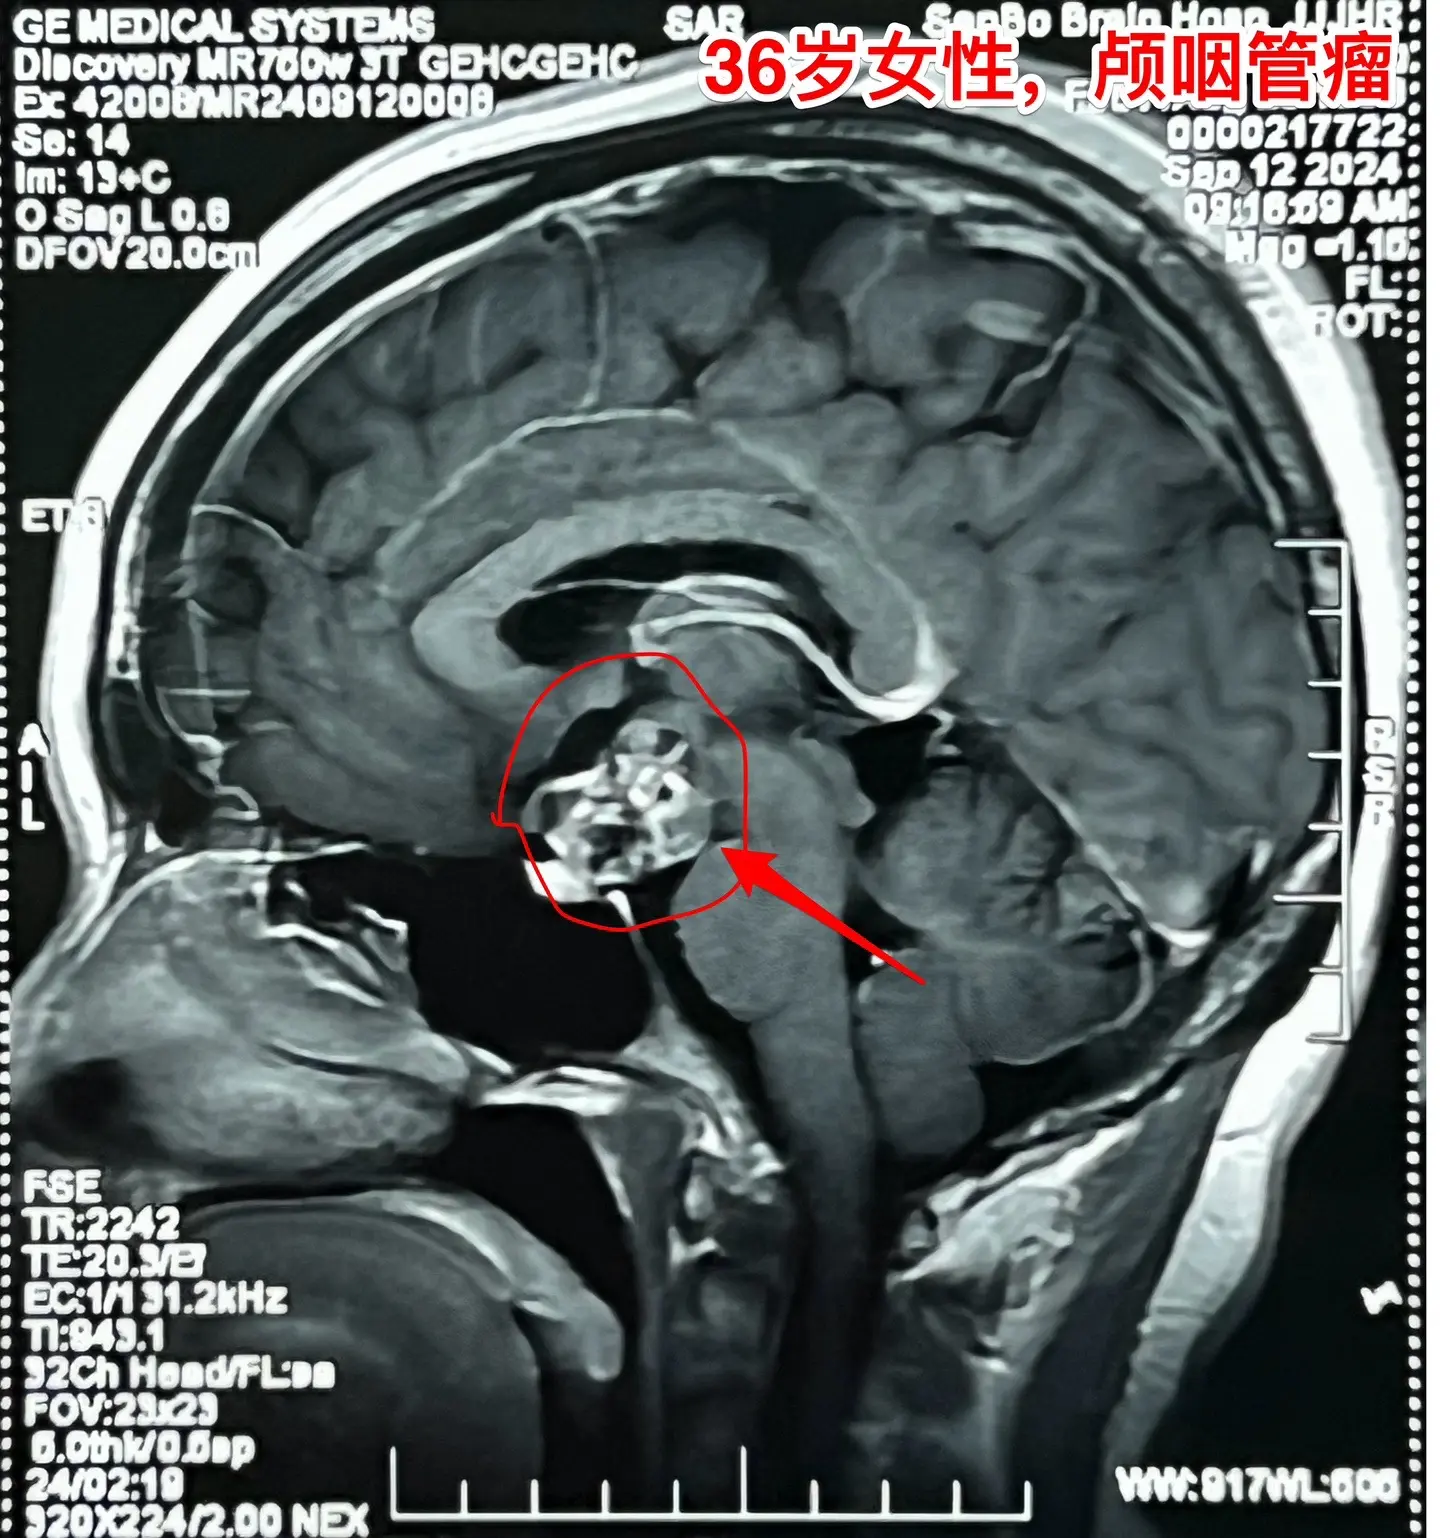

36岁玉溪市女性,颅咽管瘤手术后视力改善。一开始出现内分泌紊乱,随后出现头痛、视力下降。发现颅咽管瘤后于9月11日到我科住院,因为发烧,等到9月24日才作了手术。 好饭不怕晚!手术很顺利,肿瘤得到完全切除,垂体柄保留了30%。手术后病人的身体恢复很快,视力也好转了。